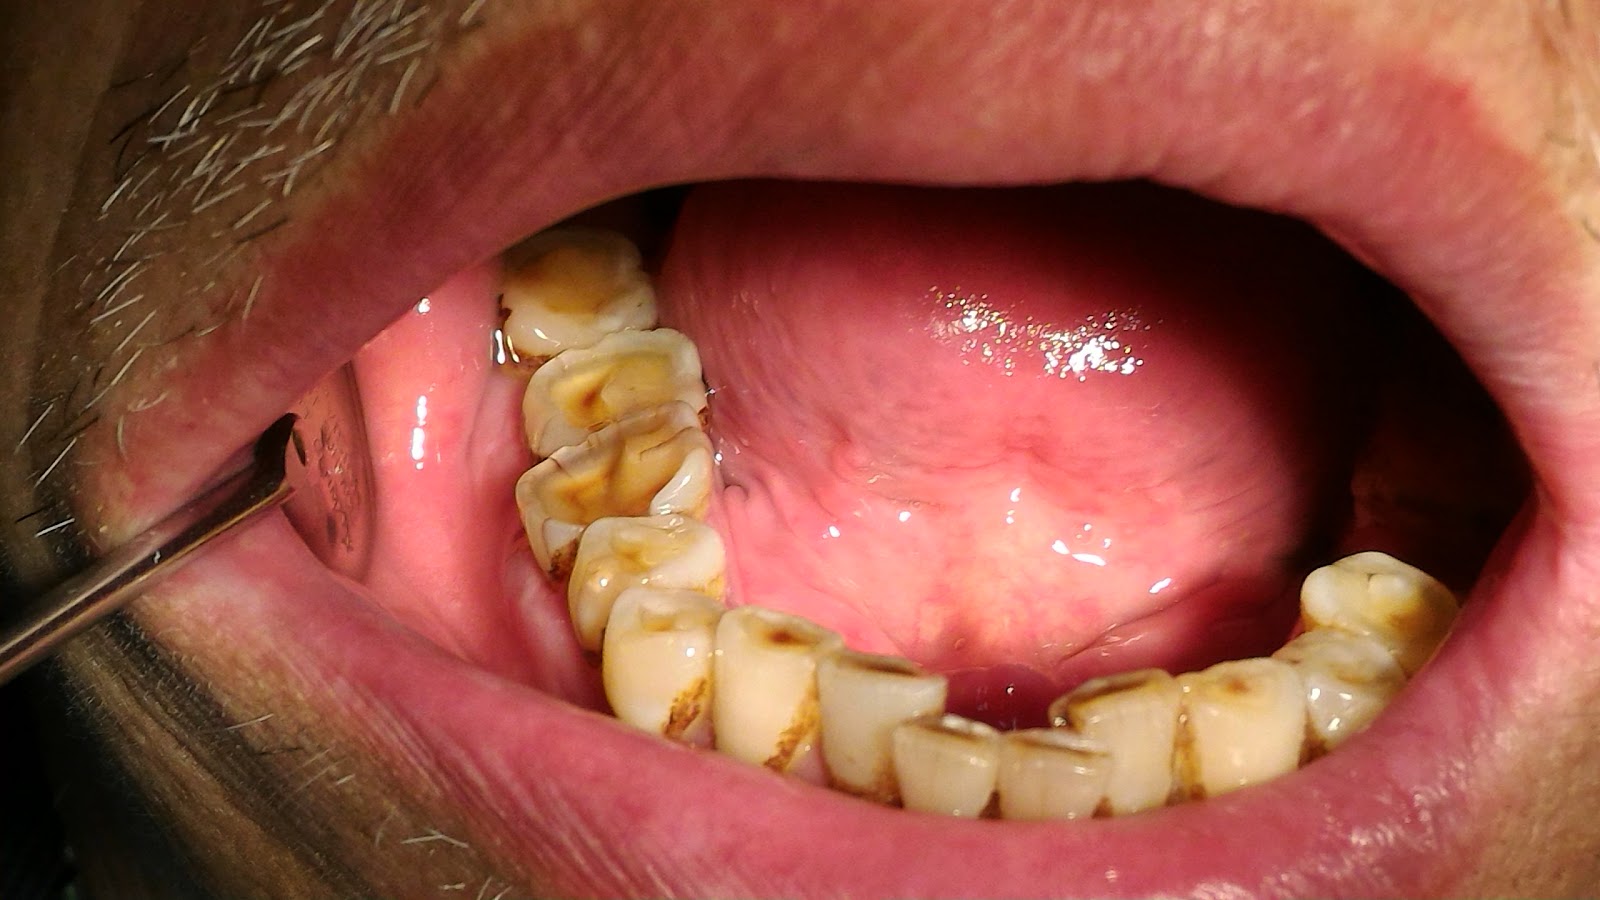

健保規定每六個月可以到牙科診所洗牙。

主要是利用超音波清除牙結石,同時做口腔檢查。

牙刷牙線有正確使用的話,多數半年還是很乾淨,也可能下顎舌側會有一點結石。

洗牙是用超音波洗牙機的震動把結石震下來。

有結石的地方才需要洗,乾淨的話不需要再用超音波震,免得傷到牙齒。

結石常見附著在牙頸部,往牙根延伸,甚至藏到牙齦下面

牙結石沒定期清除會造成牙齦發炎、萎縮,形成牙周囊袋。

牙刷刷不掉結石,必須用洗牙機清除。